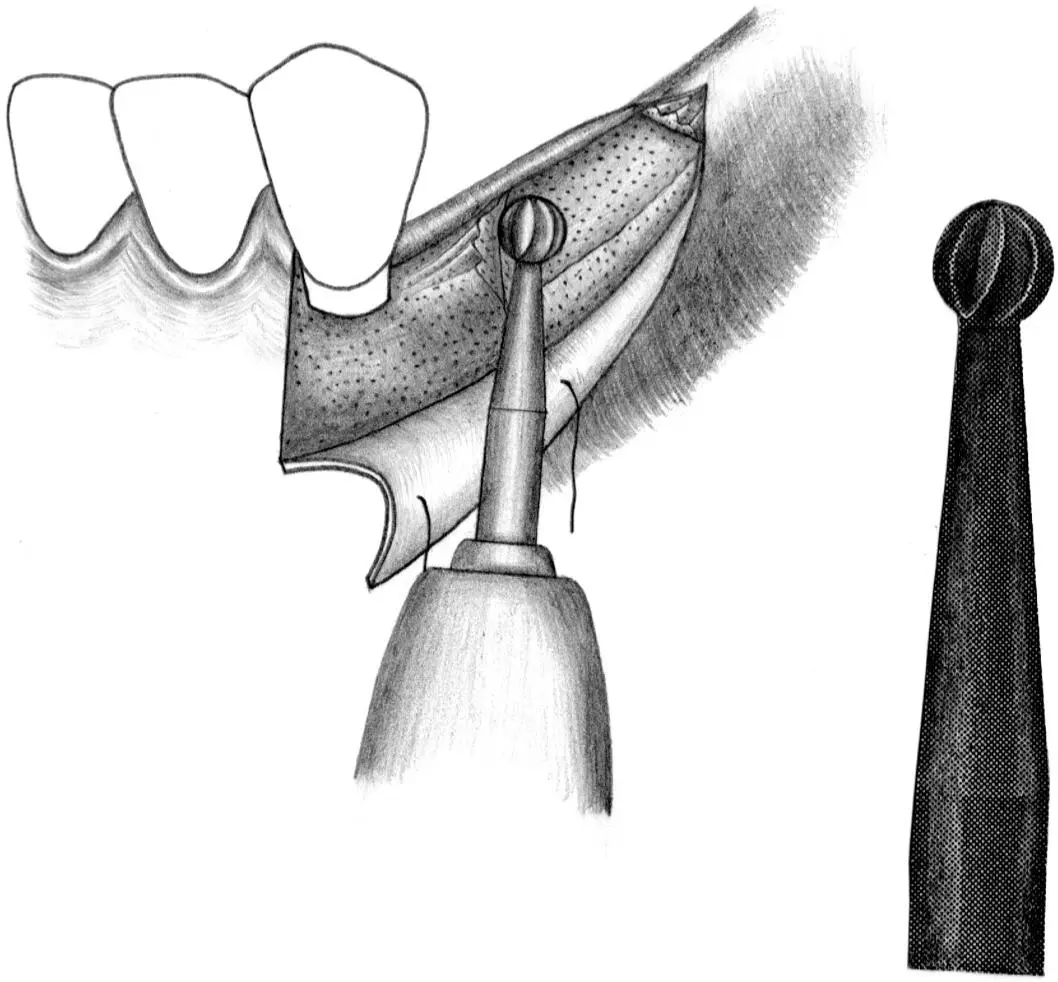

Fig 1-4 Pretapping of implant sites with bone of varying density.

Fig 1-4a Tapping of the bone in the implant site is performed when the bone structure is uniformly dense (ie, type 1 bone). This is done through the entire depth of the implant bed.

Fig 1-4b If the alveolar ridge is partially dense (ie, type 2), tapping of the implant site to one third of the predetermined depth is done within the crestal area.

Fig 1-4c When the alveolar ridge is predominantly cancellous bone (ie, types 3 and 4), no tapping of the bone is required prior to implant placement.